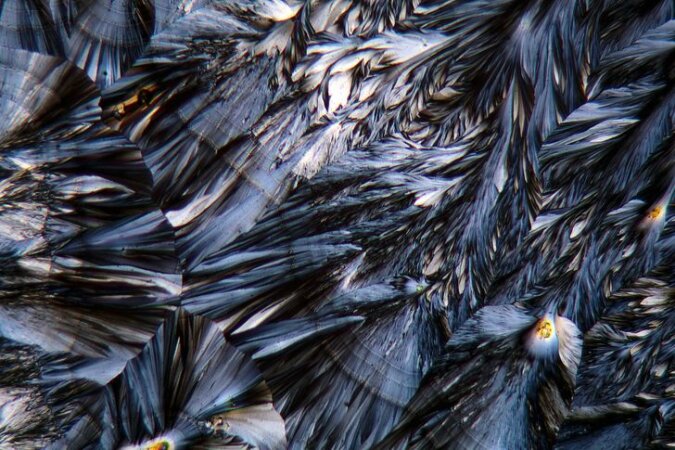

Niesamowicie piękne - to paracetamol pod mikroskopem